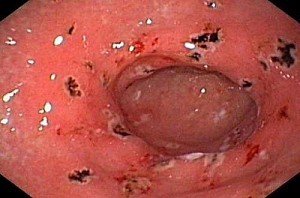

- Nội soi dạ dày – tá tràng: Giúp quan sát trực tiếp tổn thương và lấy mẫu sinh thiết nếu cần.

Hình ảnh viêm hang vị dạ dày có chấm xuất huyết qua nội soi